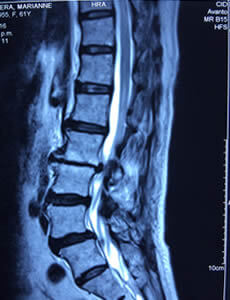

Hernia de Disto

¿Tienes una hernia de disco? ¿Dolor de Ciática? ¿Dolor de Espalda?